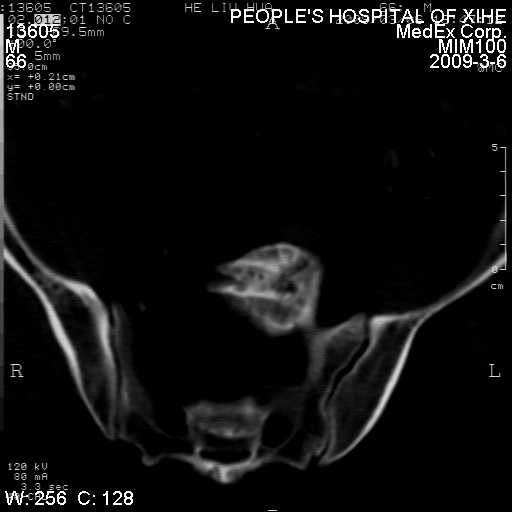

标题: CT18522:男,66岁。考虑结核有错吗 [打印本页]

标题: CT18522:男,66岁。考虑结核有错吗

x线片示:骶骨密度增高。

考虑----腰椎骶化-----退变-----椎管狭窄

腰骶椎退行性改变。

退行性变,椎体滑脱

腰椎滑脱并有退变

退行性变,椎体滑脱。建议同椎体平行进一步扫描。